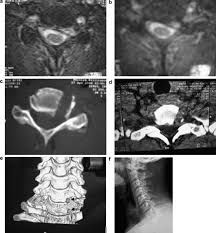

Hernia de disc cervicală înseamnă uzura şi deplasarea nucleului pulpos către canalul medular, unde comprimă o rădăcină a unui nerv spinal.

Poate fi asociată cu prezenţa osteofitelor (ciocuri) care comprimă rădăcinile nervoase şi măduva cervicală. Din pozitia culcat, asezat si din ortostatism Constientizeaza ca exercitiile pot parea diferite.

Un disc intervertebral seamănă cu o gogoașă cu. Hernia de disc face referire la o deplasare a discurilor intervertebrale care susţin coloana vertebrală. Hernia de disc cervicală are urmatoarele simptome: